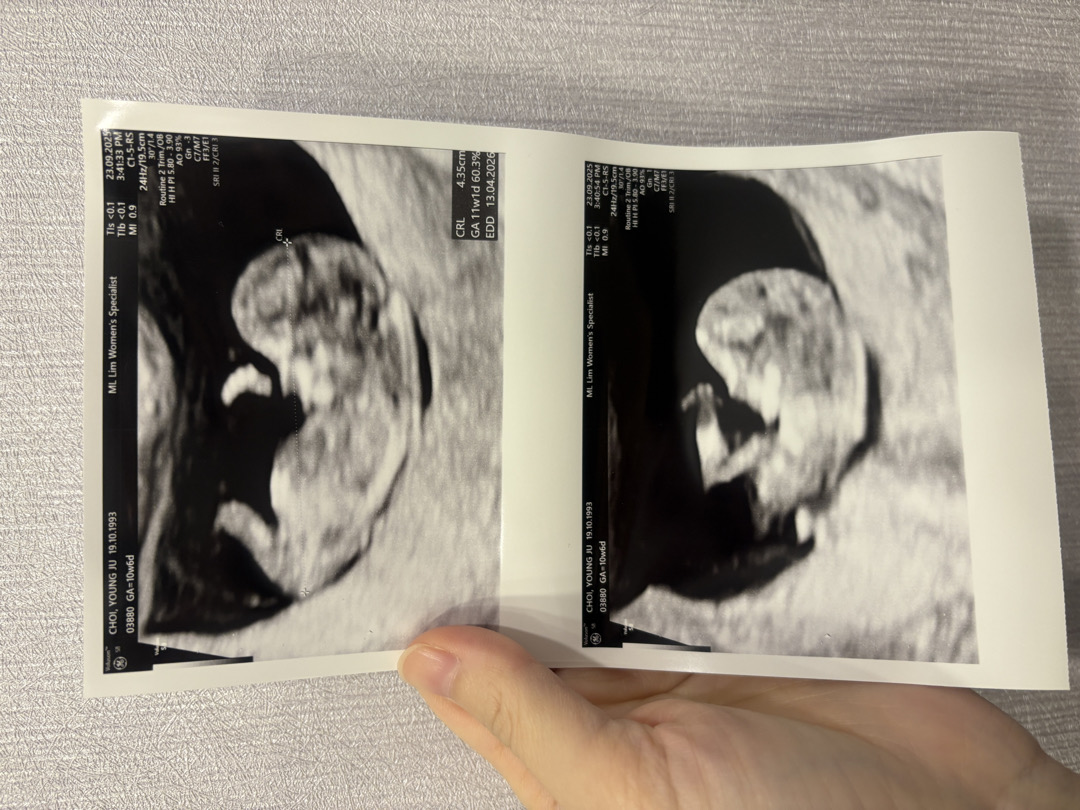

13주차이고, 11주차에 니프티검사한거 결과 나왔는데 딸맘이래요. 태몽도 아들 느낌이었고, 심장소리도 기차같았고, 평소에 좋아하지않은 단음식들 쭈쭈바, 버블밀크티가 땡겼고요, 먹덧이있지만 식욕은 임신전보다 줄어서 먹고싶은 음식이 딱히 없었어요. 피부는 원래 기름이많아 광은나지만 여드름은 항상 있었고요.. 남편이랑 저랑 아들인줄알고 다 마음먹고있었는데, 딸맘이래요! 아들이든 딸이든 다 상관없었어요. 혹시 초음파 비교해보고 싶으신분들을 위해 11주차 초음파 올려요~